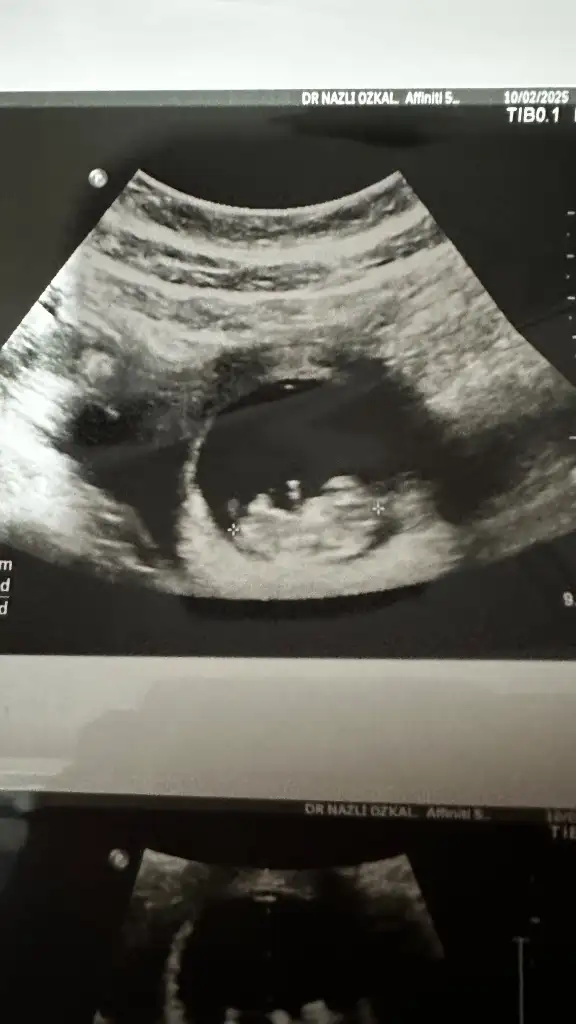

Kızar Benm kesem Nie sizinki gibi belli değil bide özelde çekildim kilodan mı7+4 Du burada şuan 8+4 olduk karından

Buda 5+6 ilk kese gözükünce